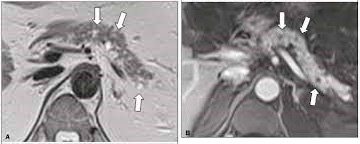

Aparece na Ressonância ou tomografia:

- lesão cística com liquido em seu interior de baixa densidade associado a septações;

- calcificação central estrelada (“Star Calcification” ou “Surnbust calcification”) ou ainda pequenos cistos conjuntos dando um aspecto em colmeia (“Honneycomb”) ou esponja (“Sponge”).

- raramente há a presença de um cisto único com parede fina chamado cistoadenoma oligocístico-macrocístico. Nos casos inconclusivos deve ser realizada a eco-endoscopia realizando biópsia da parede do cisto e dosagem de substâncias do líquido aspirado;

- células e liquido ricos em glicogênio, se atipias (células não-cancerígenas);

- tem valores baixos de marcadores tumorais como CEA(abaixo de 5), CA 19,9 (abaixo de 37,0) ,amilase normal.